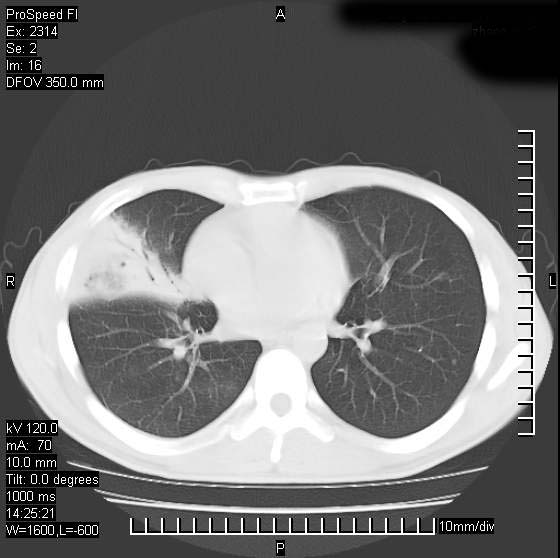

男性,再生障碍性贫血,入院前发热10天,最高40c,右侧胸痛,外院ct示右上,中肺边缘模糊的球性影(就是我现在图中标示的范围),考虑炎症,在我院使用头孢呋辛,洛美沙星10天,高烧消退,自感下午稍有发热,但今天ct示右上,中肺病灶明显扩大,还是考虑炎症,看其中的球型影是否霉菌感染??,是否能排除结核?

右肺中叶外侧段病变,上缘界限不清,下缘锐利,以段性发病为主,内见巨大空洞及空洞内容物,结合病史首先考虑:化脓性肺炎。不除外霉菌感染!

考虑霉菌感染.理由1\\有临床基础疾病,2\\有坏死的空腔,其内可见软组织影.

片状高密度影内见空洞影,内可见球形软组织密度影,并有新月征,考虑霉菌感染.